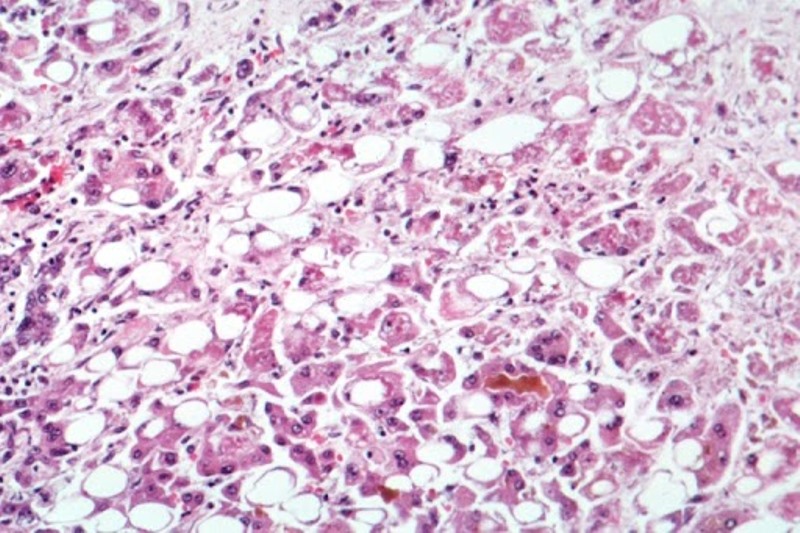

Toronto/IBNS: Cases of severe liver disease "of unknown origin" among children in Canada are being investigated by public health officials as a mysterious hepatitis outbreak has reportedly affected nearly 200 youths around the world.

According to the latest available data from the World Health Organization (WHO), at least 169 cases of acute hepatitis of unknown origin have been reported in close to a dozen countries, with 114 from the United Kingdom.

An even higher estimate of nearly 200 cases in children around the world was reported on Tuesday by the European Centre for Disease Prevention and Control (ECDC).

The cases which have been reported worldwide have struck children from one month to 16 years old.